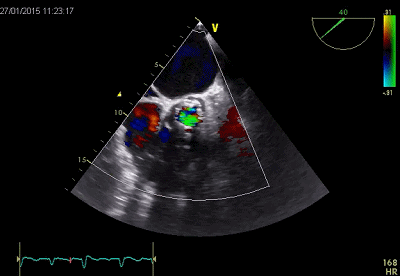

超声评价

超声提示严重MR

释放Clip后反流明显减轻

三维超声下显示二尖瓣呈双孔